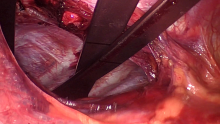

The patient was a 37-year-old female high-performance athlete with severe pectus excavatum (HI 3.5) associated with compression of the right cavities, occasional palpitations, and an episode of syncope. The surgical technique used consisted of bilateral cryoanalgesia from levels T3 to T7, sternal elevation with a traction crane, and anchoring of two screws. The cross-bar correction involved the placement of three bars guided by thoracoscopy and the fixation of the three bars with two stabilizer bridges. A flare-buster correction was performed on the associated chondral dysmorphia using a fiberloop suture. Intraoperative transesophageal echocardiography was performed before and after sternal relocation.

Correction of the thoracic deformity was achieved, as well as decompression of the right heart cavities evidenced by the intraoperative echocardiography. The patient did not experience surgical complications in the immediate postoperative period. At the three month examination, the bars were still correctly positioned and the patient had little pain with occasional intake of paracetamol.

The cross-bar technique can be applied successfully in severe cases of pectus excavatum by providing full support of the sternum. The use of a sternal elevation crane facilitates the dissection of the anterior mediastinum, potentially decreasing the risk of bleeding, hemopericardium, and cardiac tamponade. Fixing the bars with stabilizer bridges prevents bar displacement and diminishes the risk of costal erosion. The association of cryoanalgesia served to reduce postoperative pain and the need for conventional analgesia.